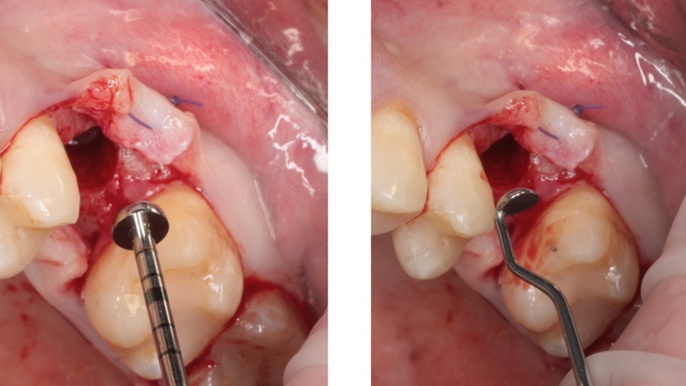

Clinical case: Installation of dental implants in complicated anatomic conditions using crest lifting methods

- Courtesy of Dr.Alexander Lysov, Russia -

AnyRidge, complicated anatomic conditions, crest lift, MICA Kit, Dr. Alexander Lysov, bone regeneration, GBR, #26, maxillary posterior

AnyRidge implant system, MICA Kit